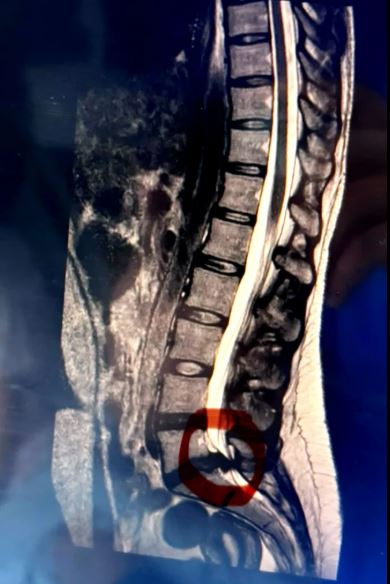

ÀÌÈÄ 3ÁÖ µ¿¾È ÅëÁõÀº Á¡Á¡ ¾Çȵưí, °©Àڱ⠸öÀÇ ¿À¸¥ÂʱîÁö ¿ÏÀüÈ÷ ¸¶ºñµÇ¸é¼ ¿ä½Ç±Ý Áõ»óÀÌ ³ªÅ¸³µ´Ù. ´Ù½Ã º´¿øÀ» ãÀº ±×´Â ôÃß ±âÀúºÎÀÇ ½Å°æ±Ù(¸¶¹Ì)ÀÌ ¾Ð¹ÚµÇ´Â Èñ±Í ÀÀ±Þ ÁúȯÀÎ ¸¶¹ÌÁõÈıº(Cauda Equina Syndrome, CES) Áø´ÜÀ» ¹Þ¾Ò´Ù. ÀÇ·áÁøÀº ±×¿¡°Ô ´Ù½Ã °È±â ¾î·Æ°í ¹æ±¤°ú Àå ±â´Éµµ ȸº¹ÇÏÁö ¸øÇÒ °¡´É¼ºÀÌ Å©´Ù°í ÀüÇß´Ù.

¸¶¹ÌÁõÈıºÀº ¸»ÃÑÁõÈıºÀ̶ó°íµµ ºÒ¸®¸ç, ôÃß ³¡ºÎºÐ¿¡¼ ¸»²¿¸®Ã³·³ »¸¾î ³ª¿Â ½Å°æ ´Ù¹ß(¸¶¹ÌÃÑ)ÀÌ µð½ºÅ© Å»ÃâÀ̳ª ¿Ü»ó µîÀ¸·Î ½ÉÇÏ°Ô ¾Ð¹Ú¹ÞÀ» ¶§ ¹ß»ýÇÏ´Â ÀÀ±Þ ÁúȯÀÌ´Ù. ¸¶¹ÌÃÑÀº ¹æ±¤, Àå, ¼º±â´ÉÀ» Á¶ÀýÇϱ⠶§¹®¿¡ ¼Õ»óµÇ¸é ÁÖ¿ä ½Åü ±â´É¿¡ Å« ¿µÇâÀ» ¹ÌÄ¥ ¼ö ÀÖ´Ù, ¹ß»ý·üÀº 10¸¸ ¸í´ç 1~3¸í Á¤µµ·Î µå¹°Áö¸¸, Ä¡·á°¡ Áö¿¬µÇ¸é Æò»ý ÈÄÀ¯ÁõÀÌ ³²À» ¼ö ÀÖ¾î Áï°¢ÀûÀÎ Ä¡·á°¡ ÇÊ¿äÇÏ´Ù. ƯÈ÷ Áõ»ó ¹ßÇö ÈÄ 24~48½Ã°£ À̳»¿¡ ¼ö¼úÇÏÁö ¾ÊÀ¸¸é ½Å°æ ¼Õ»óÀÌ °íÂøµÅ ȸº¹ÀÌ ¾î·Á¿öÁø´Ù.